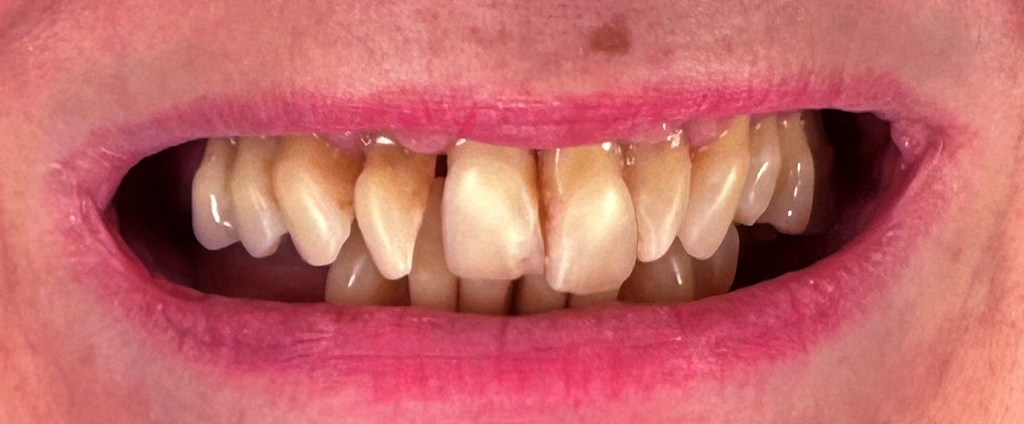

Na tym etapie rozpoczynamy proces planowania leczenia. Spotkasz się z lekarzem implantologiem oraz zostanie przeprowadzona pełna higienizacja Twoich zębów. Ponad to, pobierzemy cyfrowy wycisk jamy ustnej, wykonamy niezbędne fotografie oraz wykonamy pełną diagnostykę w celu przygotowania szablonów chirurgicznych i prac tymczasowych.